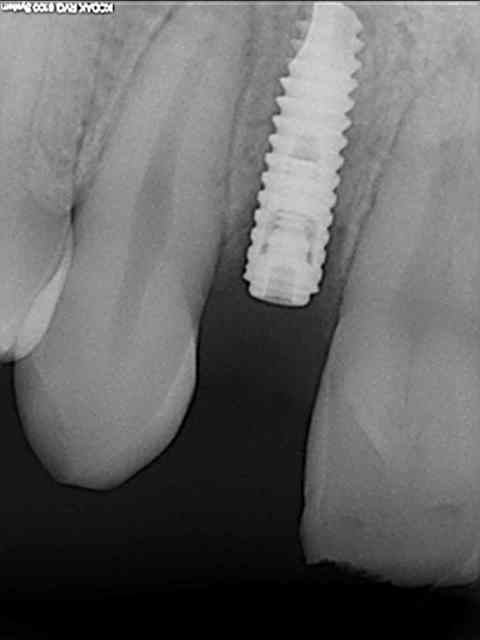

tes implants 12 et 13 n'ont pas le même niveau d'enfouissement, tu n'as pas peur d'une lyse osseuse de 13 pour venir au niveau du col de 12 ?

comment tu fais pour rester en stérile et prendre ton OPT ?

Quand je prend une RVG, je gaine le capteur et j'ai une charlotte plastic transparente sur le tube et c'est l'assistante non stérile qui appuie sur le "bouton"